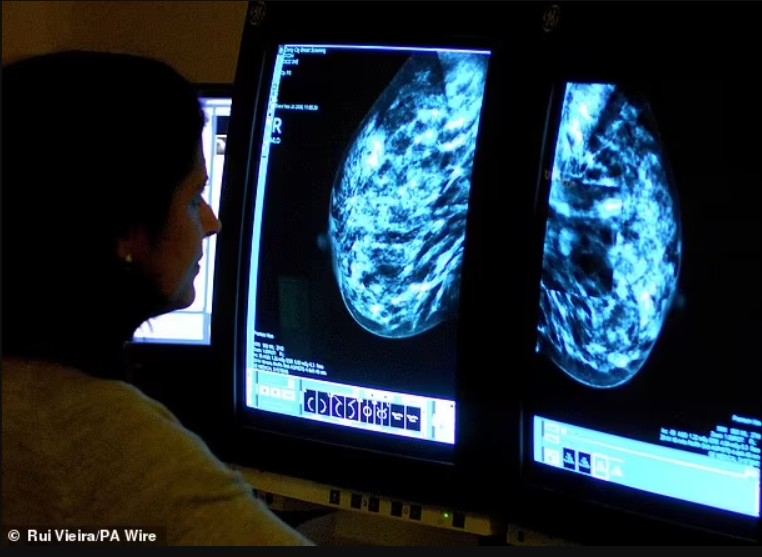

Zbulim madhor për tumoret e gjirit që janë shumë të vegjël për t’u parë në skanime